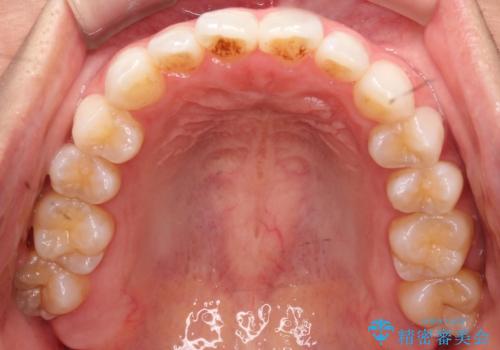

前歯の叢生を非抜歯で改善|インビザライン+IPR・遠心移動・FIX保定

- 前歯部のガタガタ(叢生)を非抜歯で改善するため、インビザラインによるマウスピース矯正を計画しました。抜歯は行わず、歯間をわずかに削るIPR(ディスキング)と奥歯を後方に移動させる遠心移動を併用して、歯を並べるスペースを確保します。歯列が整った後は、FIXリテーナー(固定式保定装置)で後戻りを防止し、安定した歯並びを維持します。

歯を抜きたくないというご希望に応え、インビザラインを用いて非抜歯で歯列を整えました。前歯に必要なスペースを確保するため、歯間をわずかに削るIPRと奥歯を後方に移動する遠心移動を組み合わせました。これにより自然で美しい歯並びを実現。治療終了後は、歯の裏側に目立たないFIXリテーナーを装着し、歯列の後戻りを効果的に防ぎました。患者様は治療中も審美的にストレスなく過ごされ、満足度の高い結果を得られました。